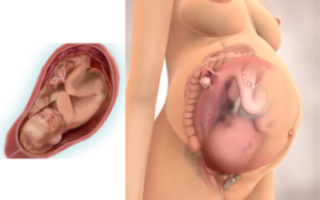

На этом сроке развития беременности матка достигает своих максимальных размеров, вес ее составляет около килограмма, а объем — 4-5 л. От лобкового симфиза ее верхушка на этом сроке находится в 37 см и в 16-17 см от пупка. Также на мочевой пузырь увеличивается давление, может возникать стреляющая боль в промежности и ногах, несколько раз в день затвердевает живот и ломит спину.

Ваша матка достигла максимальных размеров: весит около килограмма, объем – 4–5 л. Ее верхушка сейчас находится в 37 см от лобкового симфиза и в 16–17 см от пупка. Еще увеличивается давление на мочевой пузырь, живот тонизирует по несколько раз в день.

Живот на 37 неделе беременности может начать потихонечку опускаться, чему женщина будет несказанно рада: во-первых, это значит, что роды приближаются (а носить груз она уже устала – что там говорить), во-вторых, наконец-то она сможет вдохнуть воздух полной грудью (как давно этого не было!). Правда, взамен этого появятся боли и ощущение тяжести в нижней части живота и области промежности – животик начнет давить своим грузом вниз.

Впрочем, далеко не всегда живот опускается перед родами, и это является также нормой. Зато вы можете предугадать приближающиеся роды по своим ощущениям: внизу живота начинает тянуть и побаливать.